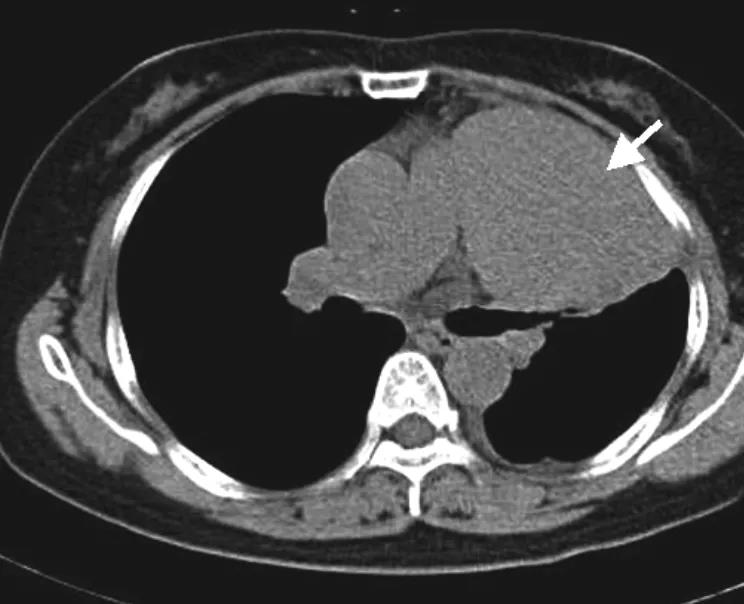

孤立性纤维瘤

孤立性纤维瘤为罕见间叶源性肿瘤,广泛分布于机体结缔组织。CT 显示孤立性肿块,边界多清楚,可见分叶,CT 平扫当瘤体较大时可见低密度区。

增强扫描时,瘤体较小时呈均匀、渐进性强化。瘤体较大时,因瘤内坏死、囊变等,肿块密度不均,增强扫描呈不均匀强化,即特征性「地图样」强化(图 8)。